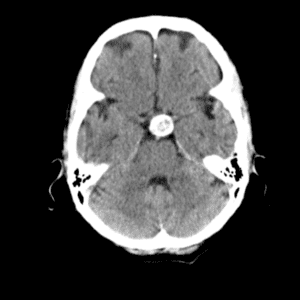

Case #11

Medulloblastoma